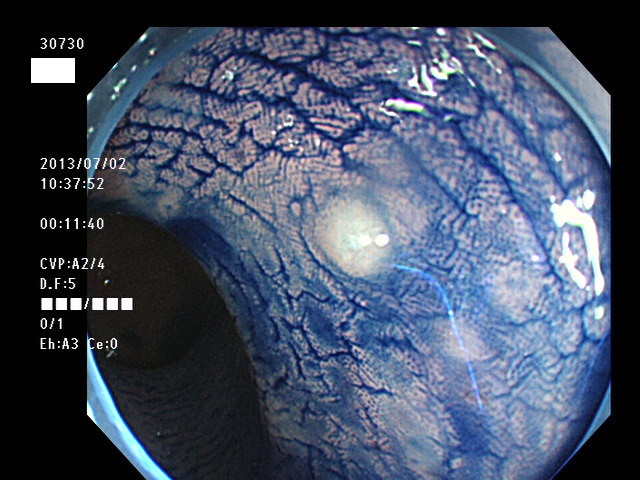

微小カルチノイドの診断

直腸の微小カルチノイドの診断は最も難しい問題です

微小とはいえ、カルチノイドは悪性であり、肛門に近い場所に好発するために、見落とすと数年後には「人工肛門」になる危険があります

進行したカルチノイドの診断は容易なのですが、カルチノイドは「粘膜下腫瘍」と言いまして、は表面が正常粘膜で被われているために微小ですと「単なる過形成結節」「単なる炎症性の隆起」と区別がつかないのです

下記の写真は全て、当院で診断された微小カルチノイド(悪性)ですが、いかに診断が困難かお分かりいただけるでしょう。このような微小病変でさえも見落とせば人工肛門の危険が潜んでいる訳です。